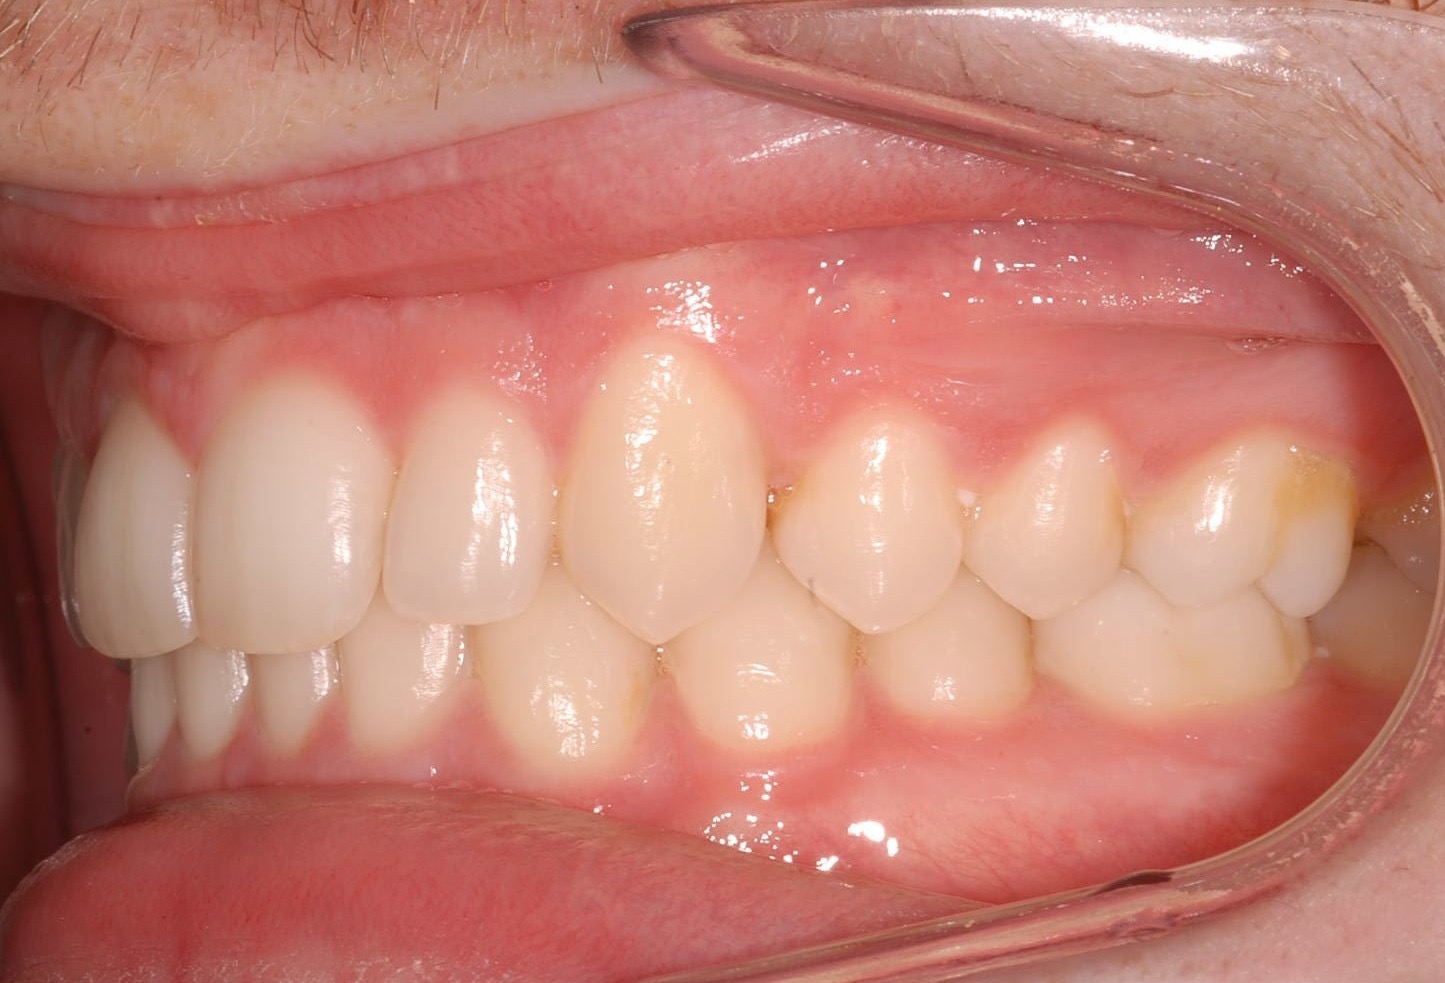

Class II subdivision malocclusions can be difficult to treat because of their asymmetric occlusal relationships. An accurate diagnosis, etiologically based when possible, is essential to perform a correct and efficient orthodontic treatment.

The aim of this article is to illustrate a case report treated with customized lingual brackets in association with a simple vestibular device.